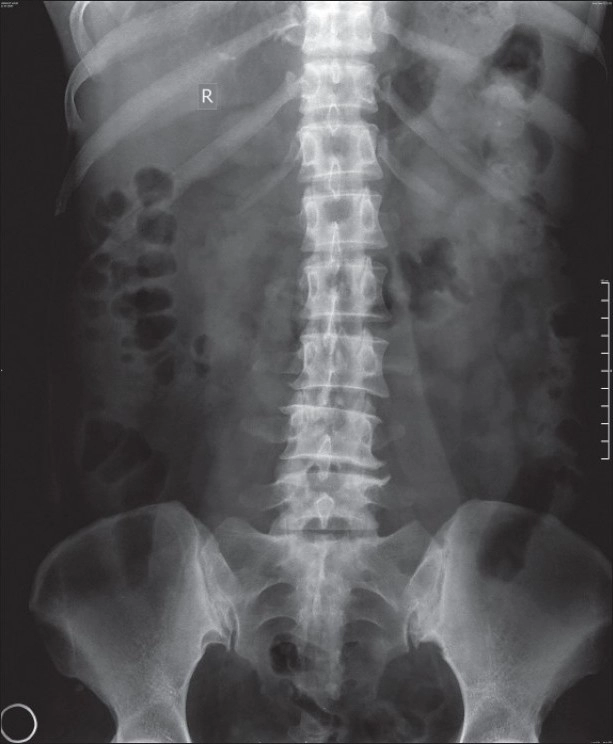

Рентген позвоночника

Рентген позвоночника – традиционный метод первичной диагностики, который обязательно назначают для выявления причин боли в спине, при травмах, возрастных или врожденных деформациях опорного столба и других патологиях костно-хрящевых структур.

В результате пропускания рентгеновских лучей через ткани человеческого тела на пленке возникает изображение, визуализирующее особенности строения позвонков и прилегающих тканей. Быстрота, высокая информативность и относительная дешевизна процедуры делают ее одним из самых востребованных диагностических методов.

В клинике «Медицина» рентген спины делают при помощи современного цифрового оборудования, которое создает уменьшенную лучевую нагрузку на организм пациента. Для этого в конструкции присутствуют электронно-оптические ускорители, минимизирующие излучение. Оцифровка изображения, снимаемого с экрана, позволяет получать снимки высокой четкости, позволяющие предельно точно определять характер патологии.

Диагностика позволяет выявить ряд патологий костно-хрящевой структуры позвоночного столба и прилегающих тканей – мышечной, соединительной и др. Рентгеновские снимки показывают наличие остеопороза, остеохондроза, различных деформаций позвонков и межпозвоночных тканей, новообразований, воспалительных процессов, врожденных аномалий, туберкулеза. С их помощью обнаруживают трещины и переломы позвоночника, кровоизлияния, гематомы и другие травматические повреждения

Рентгеновское исследование, как правило, проводят в специально оборудованном кабинете клиники, но благодаря наличию портативных мобильных аппаратов сделать снимки можно в палате стационара и даже на дому. Для просвечивания рентгеновскими лучами больного помещают между излучателем и приемным устройством. Процедура абсолютно безболезненна и проводится без проникновения в тело пациента. Съемка одного изображения занимает 2-3 секунды, для диагностики обычно делают два-три снимка в различных проекциях.